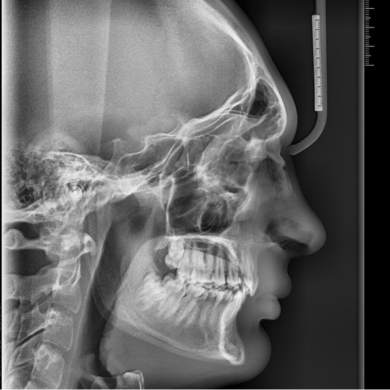

لترال سفالومتری

این عکس به بررسی روابط اسکلتی فک بالا و پایین، الگوی رشد، فرم صورت و پروفایل کمک میکنه. در بیمارانی که ناهنجاریهای اسکلتی دارند یا تصمیمات درمانی مهمی پیش روست، لترال سفالومتری نقش کلیدی داره.

نکته:

هنگام گرفتن عکس حتما به رادیولوژیست تاکید کن که مهره های گردنی مشخص باشد

مخصوصا برای اطفال.